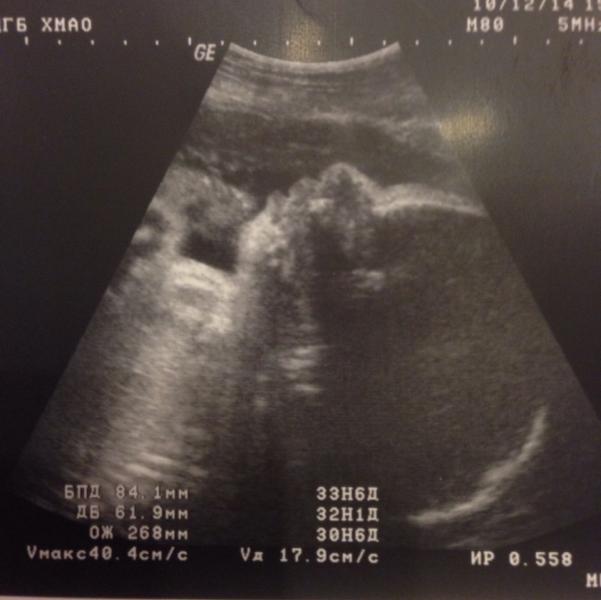

Девочки девчули!всем привет! Сегодня была на последнем плановом узи) вышла довольная как слон. Во-первых, у моей Виты все хорошо,голова у нас внизу попка наверху все как надо, вод норм кол-во,во -вторых обвития нет( а то я очень переживала), весим мы 1850кг, и в третьих я выпросила у врача фотку( говорю ей ну хоть личико хоть может ручку,ну хоть что нибудь), она ловила ловила и сфоткала нас в профиль😊😊😊Вита очень крутилась и икала очень сложно было поймать. Моему счастью нет предела наверно сего...